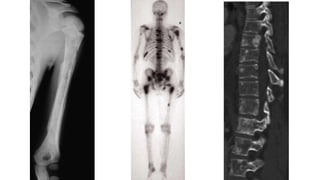

Metastatic malignant tumors are by far the

commonest bone neoplasm

Radionuclide bone scans show substantially increased

activity in the lesion.

MRI isthe most accurate technique forshowing the

extension into both the medullary cavity and the soft

tissues can be accurately defined, as can the

relationship to important nerves and blood vessels.

MRI provides this information better than CT

1. Metastases:

🠶Commonest malignant bone tumour

🠶Metastases may be sclerotic, lytic or a mixed.

🠶 Bones mostly affected are those containing red marrow:

the spine, skull, ribs, pelvis, humeri and femora.

🠶Most of metastases are lytic

🠶Metastases and myeloma are virtually the only causes of

multiple obvious lytic lesions in bone.

🠶Sclerotic metastases: mainly from prostate CA in male

and breast CA in female

🠶Mixed lytic –sclerotic metastasis are mainly from breast

CA.

🠶Metastases with bone expansion occur in primary

tumours of the kidney and thyroid.

🠶Neuroblastoma metastasis may cause periosteal

reaction

🠶Radionuclide bone scan: best modality, reveals 30%of

lesions that are not evident on X ray.

🠶 MRI: better sensitivity than radionuclide. Disadvantage?

🠶 CT scan: less sensitive than MRI, need bone window